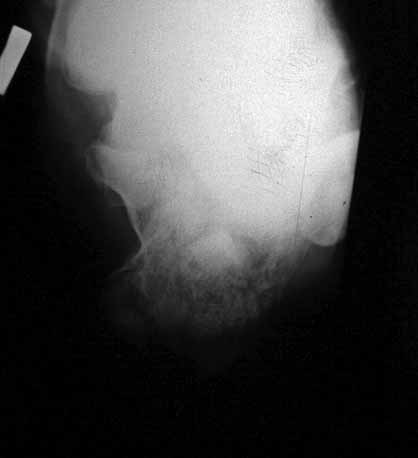

КТ перелома пяточной кости

Пациент 60 лет с производственной травмой-закрытые переломы правой пяточной кости, тибиального плато слева поступил в феврале с.г. На 4 сутки выполнена открытая репозиция, остеосинтез внутрисуставного перелома голени, ручная репозиция пяточной кости. Через три месяца начал ходить с нагрузкой на обе ноги. Консолидация голени с полным восстановлением функции колена. Правая стопа умеренно отечна, продольно распластана, длительная ходьба вызывает боли и увеличение отека. Прошел несколько курсов ударно-волновой терапии, грязелечение, боли и отек уменьшились. В наших планах -оформление на ВТЭК, через год возможно выполнение подтаранного артродеза.Но после производства КТ в августе появились сомнения в консолидации перелома.Ранее у нас не было опыта КТ переломов стопы и сканы привели в замешательство.Прилагаю снимки со дня поступления, августовские пациентом не представлены.С благодарностью примем советы коллег.